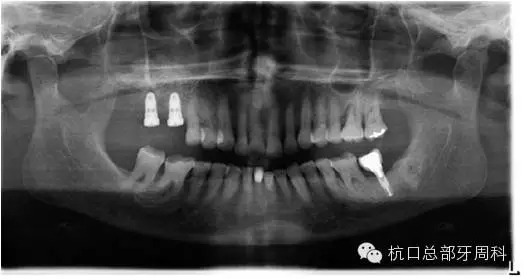

種植后即刻拍片  2005

110.webp.jpg

被診斷為種周炎時(shí)全景片  2011

111.webp.jpg